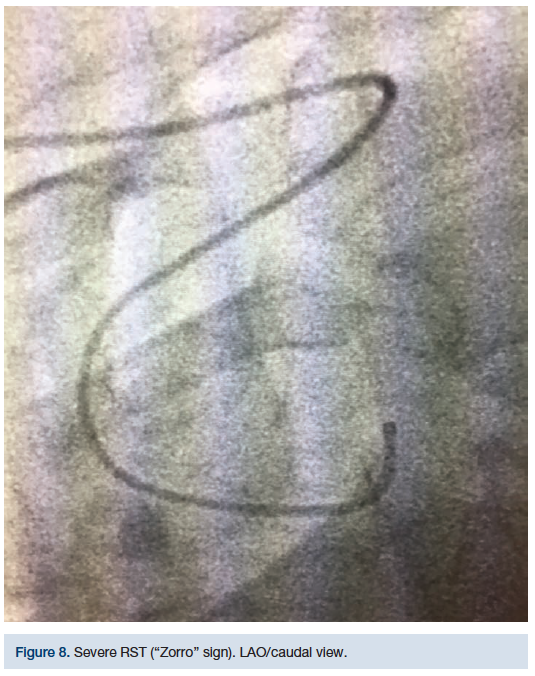

This technique was initially used on a 68-year-old female, diabetic, 5 feet, 4 inches tall, hypertensive, with severe RST (Figures 5-8). Despite several different catheter positions, wires, and extensive deep inspirations, the wire was repeatedly biased towards the descending aorta. Prior to bailing out to an alternative approach, we hypothesized that doing the exact opposite might gain us access to the AA. After several minutes of fluoroscopy and extensive deep inspirations disallowed navigation, a single deep expiration allowed our wire and catheter access into the AA with minimal fluoroscopy.